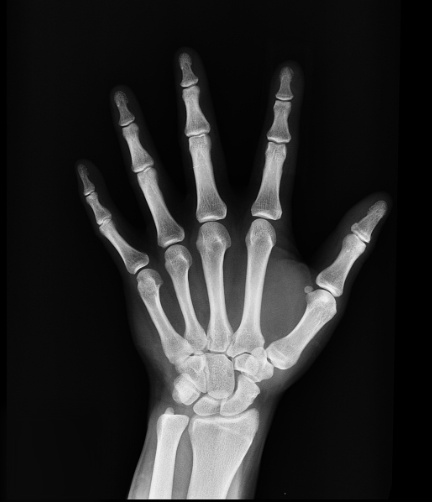

뼈는 우리 몸을 지탱하고 활동을 지원하는 중요한 부분입니다. 그러나 골다공증은 뼈의 밀도가 감소하여 취약해지고 쉽게 골절이 발생하는 만성적인 질환입니다. 골다공증 주사는 이러한 뼈 건강 문제를 예방하거나 치료하기 위해 사용되는 효과적인 치료 방법 중 하나입니다. 골다공증 주사는 골다공증 약물을 혈관이나 근육에 주입하여 뼈 손상을 최소화하고 뼈의 밀도를 증가시켜줍니다. 이로써 환자는 골다공증으로 인한 골절 위험을 감소시키고 뼈 건강을 유지할 수 있습니다. 아래의 글에서는 골다공증 주사 종류 및 골다공증 주사 6개월 주기로 맞아야 하는지 알아보겠습니다.

골다공증 주사는 주로 골다공증 예방이나 치료를 위해 사용되는 약물을 혈관 내 또는 근육에 주입하는 치료 방법입니다. 골다공증 주사 치료는 뼈의 손상을 최소화하고 뼈 밀도를 증가시켜 골다공증의 진행을 억제하는데 사용됩니다. 다양한 골다공증 주사 약물이 있으며 주로 다음과 같은 유형이 사용됩니다.